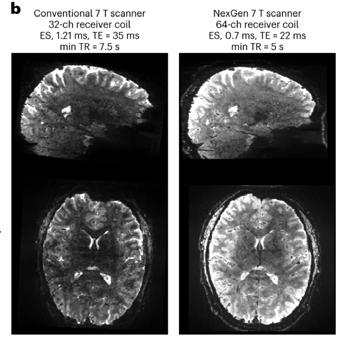

Next Gen 7T MRI Allows Neuroimaging with Unprecedented Precision

Conventional MRI scanners for clinical use generate images using magnets whose strength is measured at 1.5 Tesla (T) or 3T. At a limited number of locations across the world, clinicians and researchers have access to MRI scanners with much more powerful magnets operating at 7T. With the several dozen 7T machines located in the United States, imaging scientists can gain much higher resolution images, examining the tiny details that make up the architecture of the brain and body. However, there is still a ceiling to that resolution, as even with the most optimal scan parameters, features smaller than one to two millimeters vanish into the abstraction of the voxel, a three-dimensional pixel.

In December 2023, an international team of scientists including UCSF faculty member An (Joseph) Vu, PhD, broke that ceiling. Led by UC Berkeley professor and president of Advanced MRI Technologies, David Feinberg, PhD, MD, the team is a multi-institution collaboration with scientists from UCSF including Drs. An (Joseph) Vu and Pratik Mukherjee, UC Berkeley, Harvard, Siemens Healthineers (Erlangen, Germany), Advanced MRI Technologies (Sebastopol, CA), and MR CoilTech LTD (Glasgow, UK). Together, they constructed a next generation ultra-high resolution 7T MRI scanner, which achieves up to 10-fold increase in resolution over the current 7T standard, which is 50 times more detail than the hospital standard 3T scanners. With this new tool, functional images can now be captured with a voxel size of less than half a millimeter. This allows scientists to, for the first time, image functional clusters of neurons across

the entire brain, organized in cortical cell layers and cortical columns, opening up the study of a new realm of meso-scale local neurocircuitry.

Thanks to additional funding obtained by Drs. Vu, Feinberg, and Alexander Beckett, the NexGen 7T is now available to scientists across the Weill Neurohub consortium of UCSF, UC Berkeley, and the University of Washington, and as an international resource through the NIH BRAIN Initiative. The NexGen 7T MRI scanner is described in a Nature Methods article “Next-generation MRI scanner designed for ultra-high-resolution human brain imaging at 7 Tesla.”1

Although the NexGen 7T is not yet FDA approved, it has achieved remarkable breakthroughs in fast, high-resolution neuroimaging by virtue of several key advancements: an extremely powerful head gradient system, the first 128 channel receiver systems integrated into a 7T scanner, and several universally optimized RF pulse sequence protocol.

NexGen 7T 0.6 mm isotropic diffusion images (b=0 s/mm2) depicting fine anatomical structures including hippocampal layers and perivascular spaces.

commercially available 7T scanners. This advancement in gradient performance was achieved with a novel 3-layer wire winding design instead of only two layers. The faster and stronger the magnetic gradients are, the faster the MRI data can be encoded, fighting the clock of T2 signal decay and blurring. There were a lot of physics challenges to achieve such strong and fast gradients. In addition to the need to minimize peripheral nerve stimulation effects, the mechanical forces interacting with the field and the sound pressure levels both increase as the main magnetic field gets stronger. These challenges were detailed in “Acoustic noise reduction in the NexGen 7 T scanner.”2 For all these reasons, the scanner needed to be designed at a system-wide level, factoring in RF coil design, gradient coil design, and magnet design.

Another breakthrough came via the development of 64 channel and 96 channel receiver arrays coupled with the 128-channel receiver system, vastly improving on the standard 32 channel system in terms of SNR and the ability to accelerete the imaging. As the number of receiver channels increases, the size of the individual coil loops in the head coils become smaller, which in turn provides higher sensitivity and improved ability to accelerate data acquisition for fast, ultra-high resolution functional and structural MRI.

The improvements are not only related to hardware, as RF pulse sequence design has played a great role in these milestone achievements. In collaboration with Dr. Nicolas Boulant (CEA, NeuroSpin, France), the team has implemented precisely pre-calibrated universal pulses which can produce structural images of exquisite quality on almost any subject you place inside the scanner without the need for lengthy pre-scans or subject-specific calibrations. Furthermore, in two collaborations with Dr. Renzo Huber (NIMH, NIH) and with Dr. Suhyung Park (Chonnam National University, S. Korea), improvements in functional imaging pulse sequences more precisely identify neuronal activity in cortical layers, and similar resolution gains in collaboration by achieving unprecedented isotropic resolution in the 0.35mm – 0.6mm range.

Feinberg points out, “The NexGen 7T scanner achieves greatly improved precision in diffusion imaging of axonal fiber tracks from the cumulative gains of high signal from 7T and the much stronger gradient encoding, now possible. Secondly, the scanner’s ability to achieve

mesoscale functional imaging at depths in the cortex rather than averaging across the cortex provides more precise information to take new directions in neurocircuitry studies of different neurological disorders including depression, chronic pain, localization in epilepsy and revealing the underpinnings of many cognitive disorders.”

Vu is excited about the new avenues this next-gen 7T scanner will open up, explaining that “Traditionally, the RF pulse sequence optimization is a very involved process done on a per subject basis. One had to acquire calibration scans, model the head, and calculate how best to excite the whole brain. Not every 7T site has the time, expertise, and capability for such an optimized scan protocol. However, with the new universal pulses pre-calibrated technique the images come out very nice on any subject, right out of the box. In the past, some clinicians and collaborators have been hesitant to go to 7T because such technology was not readily available. But with these new NexGen 7T technologies, it removes the hesitancy bottleneck for wide-spread adoption into clinical neuroimaging and research. It is a game changer!”

NexGen 7T 0.9 mm isotropic diffusion tensor images showing impressive anatomical quality and detail throughout the brain.